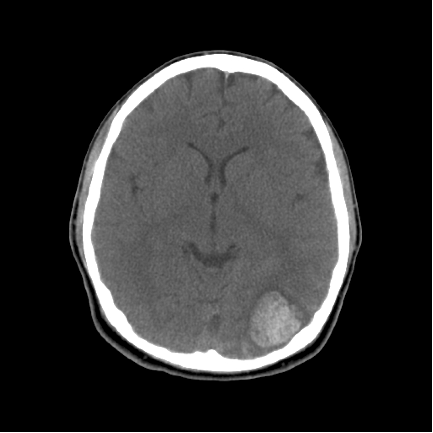

(CT Scan of Hemorrhage)